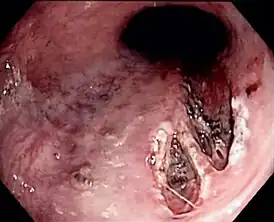

Синдром Мэ́ллори — Ве́йсса (по МКБ-10: желудочно-пищеводный разрывно-геморрагический синдром) — образование острых линейных разрывов слизистой оболочки брюшного отдела пищевода и кардиального отдела желудка при рецидивирующей рвоте, сопровождающиеся кровотечением.

Диагноз уточняют при эндоскопическом исследовании, в процессе которого, как правило, удаётся надёжно остановить кровотечение.